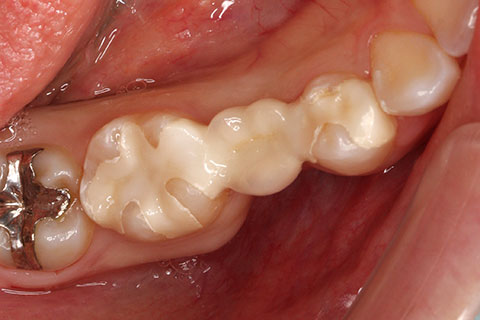

セラミックインレーの症例1

- 年齢・性別

- 30歳女性

- 治療期間

- 1ヶ月

- 抜歯

- なし

- 治療費

- 11万円

- 備考

- 奥歯2本の銀歯をセラミックにやりかえ。

- 治療内容

- 歯質を削除し、セラミックインレーをセメント合着

- 施術の副作用(リスク)

- 知覚過敏